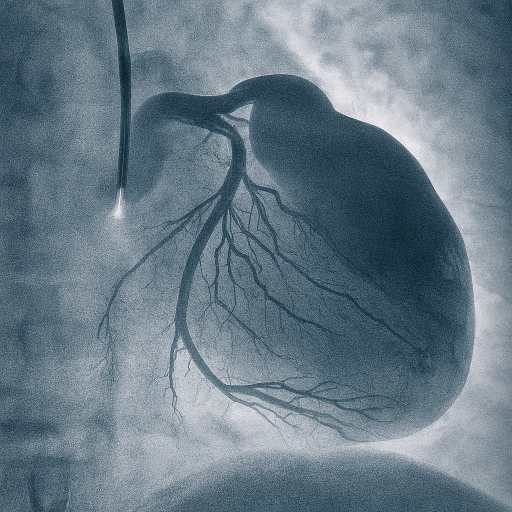

آنژیوگرافی

آنژیوگرافی قلب برای بررسی دقیق رگهای کرونر و تشخیص تنگی یا انسداد آنهاست. با تزریق ماده حاجب و تصویربرداری، مسیر خونرسانی به قلب آشکار میشود و ما میتوانیم بر پایه یافتههای علمی، درمان مناسب مانند باز کردن رگ یا جراحی را انتخاب کنیم. این خدمت با کاهش خطر سکته قلبی و پیشگیری از عوارض جدی، نقشی اساسی در ارتقای سلامت بیماران ایفا میکند.آنژیوگرافی امکان ارزیابی میزان کارایی درمانهای پیشین و پایش وضعیت بیماران را فراهم میسازد و به عنوان ابزاری علمی و قابل اعتماد، مسیر تصمیمگیری بالینی را روشنتر میکند.